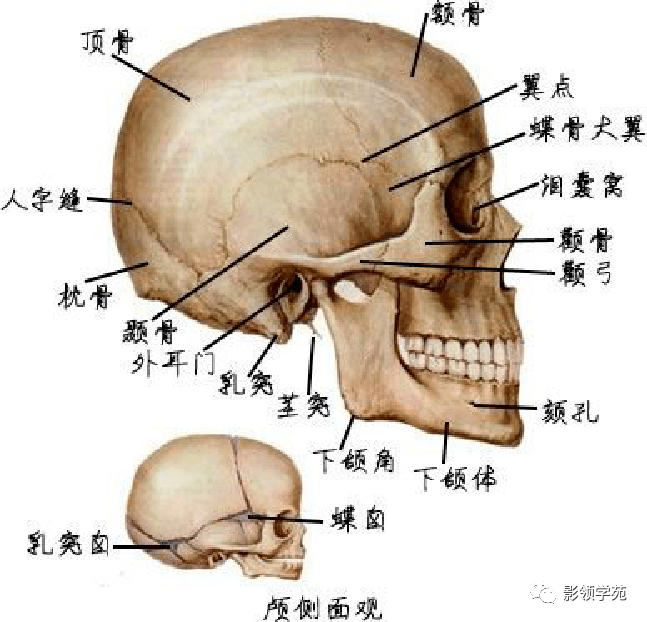

骨骼系统

骨骼系统